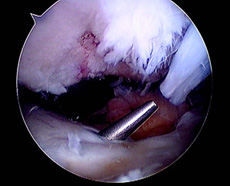

En todos los pacientes de ésta muestra fueron evaluadas radiografías y RMI para determinar las causas de la falla, dividiéndo a los pacientes en 2 grupos en virtud de si las cirugía primaria había sido efectuada por nuestro grupo de trabajo ó por otro. La causa más frecuente de fracaso en nuestra muestra fue el error técnico (75,8%), correspondiendo sólo el 46,8% a un túnel femoral anterior y el 28,5% a un túnel tibial posterior. (Figs.1, 2 y 3)

![]() |

|

Figura 1: RX Cross pin protuyendo en artic. Patelofemoral. |

Figura 2: RMI Corte sagital. Combinación de túneles femoral y tibial anteriores. |

Figura 3: Cross pin protruyendo en articulación patelofemoral por túnel femoral anterior |